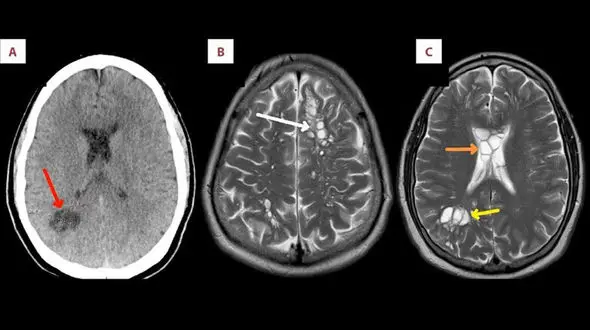

رکنا: مرد ۵۲ ساله از میگرن رنج برده و ۴ ماهی بود که دیگر داروها جواب نمیدادند و به همین خاطر به متخصصین مراجعه کرد. پزشکان با اسکن مغزی متوجه شدند وی کرم نواری گوشت خوک دارد که دلیلش خوردن بیکن نیم…